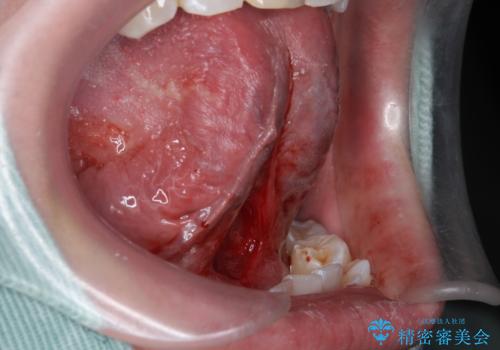

- 滑舌が気になるため舌小帯を切りたいとのことで来院された患者様です。

舌小帯切除を行い、滑舌の改善をはかります。